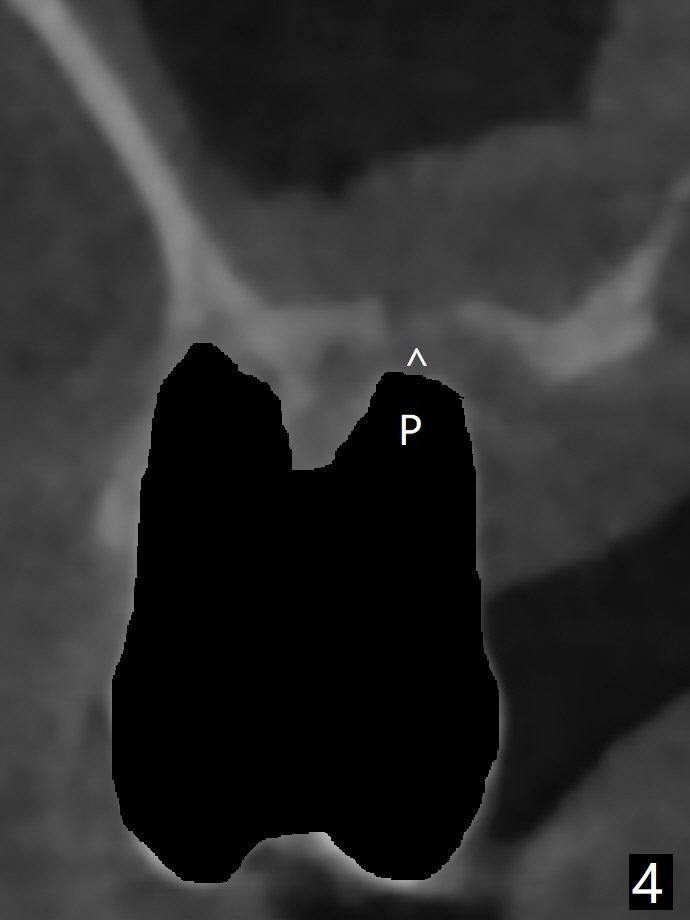

尽管右上第一,二磨牙骨质吸收严重,为了保持牙乳头,先拔除有症状第二磨牙,但是后者牙槽窝与第一磨牙之间好像没有软组织(图二:*),所以骨粉(图一,二:7)无法从前者推入后者(图二(下一个成功病例))。骨粉表面放置6个月吸收膜(GEM Cap(图三::C)),使用牙周胶水固定,而且装置牙齿空间维持器(图二:S)和牙周敷料强化固位。牙齿拔除证实腭侧牙槽窝(图四:P)上颌窦底板穿孔(^;但是没有漏气)。虽然病人已经服用Amoxicillin一周以及Z Pack(两颗,术前),为了防止感染介入上颌窦,穿孔冠部放置胶原塞(图五:黄色),然后放置骨粉(红色)。后者仿佛增加骨质高度不少(图二)。如果不够,以后再做提升。多亏间隙保持器,牙周敷料术后4天没有松动迹象(图六)。术后三周敷料颊侧有些破裂(图七),而舌侧完整(图八)。嘱咐病人正常刷牙和水牙线,让敷料自行脱落。其实术后六周敷料仍在原位,不可吸收膜粘附于敷料,两者一起去除,伤口愈合(图九),骨粉好像没有损失(图十)骨高度减少。术后4个月骨质高度继续减少(图十一)。植骨后骨质高度还与邻牙一致,密度低,可植入5x7.3毫米植体(图十二)。